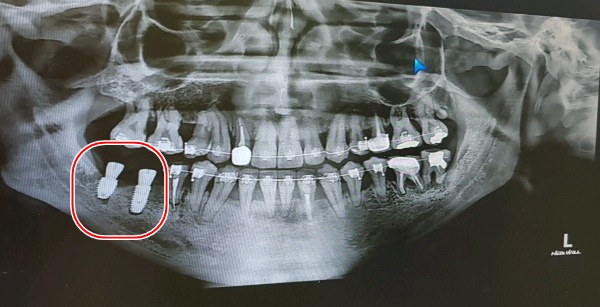

거즈를 물라고 하고 수술이 잘 됐는지 확인차 엑스레이 한번 찍고

다시 또 작업하고, 또 엑스레이 실로 가고를 1번 반복 후 이제 거의다 됐다면서

그렇게 오른쪽 임플란트 작업은 드디어 끝!!

어금니쪽이라 임플란트를 좀 큰 걸로 한건지는 모르겠으나 왜이리 커보이는지;;